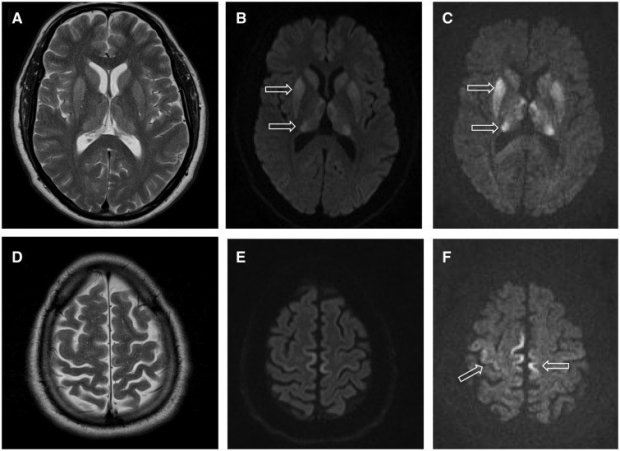

Quale che sia il fattore scatenante, ciò che si osserva in maniera simile in queste patologie è la formazione di veri e propri buchi all’interno del tessuto nervoso, che conferiscono allo stesso una struttura spongiforme. La sostanziale disgregazione della normale citoarchitettura neurale si traduce quindi in demenza, atassia (incapacità di rimanere in equilibrio e di coordinare i movimenti), convulsioni e, nell’essere umano, disturbi del comportamento e della personalità.

Tuttavia, per la CJD e per altre patologie prioniche, parlare di una vera e propria diagnosi non è possibile, fino a quando non è ormai troppo tardi. “In accordo con le linee guida dell’Organizzazione Mondiale della Sanità, che EuroCJD ha contribuito a stilare e aggiornare, a oggi la diagnosi definitiva si raggiunge solo post mortem, tramite un’accurata analisi istopatologica del tessuto cerebrale” spiega infatti il ricercatore.